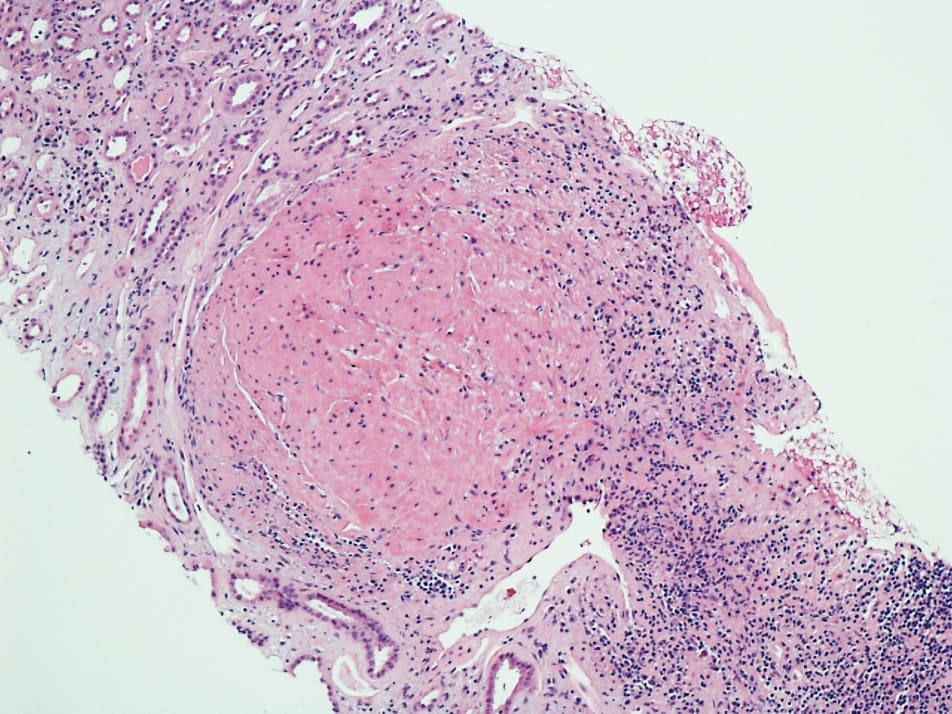

There was a small well circumscribed Leiomyoma which was reported as an incidental finding. Whorls of bland spindle cells lacking mitotic figures (Image 2, 3) were noted. Biopsy also showed hypertensive and diabetic nephrosclerosis of the vessels. Upon additional questioning, it was noted that the patient had stopped her immunosuppressive medications five months prior to this presentation with acute renal failure. She had received a living related donor renal transplant, 4 years ago with zero HLA mismatch. The donor and recipient were positive for EBV and Cytomegalovirus (CMV) antibodies. Post-transplant immunosuppression regimen consisted of Tacrolimus (calcineurin inhibitor) and Everolimus (mammalian target of rapamycin inhibitor, mTORi).

Differential diagnoses for Leiomyoma in the graft were Leiomyosarcoma, angiomyolipoma, and renal cell carcinoma [4,5]. These were ruled out based on histologic findings. Leiomyoma in the presented case histologically consisted of whorls of cytologically bland spindle cells with abundant eosinophilic cytoplasm (Image 1). On high resolution microscopy, it revealed absence of cytologic atypia and mitotic figures (Image 2).

Image 2: Low-power view showing leiomyoma with whorls of cytologically bland spindle cells and prominent eosinophilic cytoplasm.